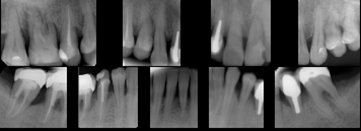

Onemocnění parodontu patří ke druhému nejčastějšímu onemocnění v dutině ústní, ihned po zubním kazu. Nejčastějším problémem je gingivitis- zánět dásní a také parodontitis - zánětlivé onemocnění postihující závěsný aparát zubů, přilehlou dáseň i kost. Mezi časné projevy gingivitidy patří krvácení dásní, které může v případě parodontitidy přejít ve tvorbu parodontálních chobotů, spojené se zápachem z úst, tvorbou hnisu, bolestmi a viklavostí zubů v důsledku ztráty kosti. Tomuto onemocnění se dá úspěšně předcházet pravidelnými kontrolami, sanací chrupu a péčí v rámci dentální hygieny.

Periometr - první plně automatizovaný přístroj pro zjištění periodontálního statusu pacienta - diagnózy, léčby a profylaxe parodontitidy a dalších onemocnění. Díky správnému určení periodontálnímu statusu pacienta lze včas odhalit a minimalizovat objevující se obtíže.

Používá se i v implantologii, při stanovení diagnózy a léčby periimplantitidy (zánětu měkkých tkání a kosti v okolí implantátu).